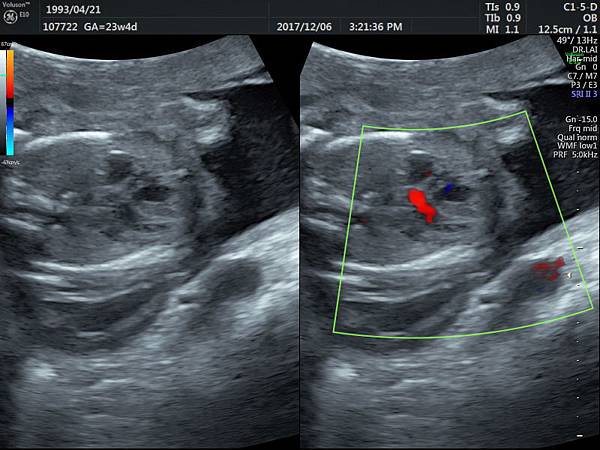

有一對夫妻因為我之前迷走性右側鎖骨下動脈(ARSA)的診斷而選擇孕兒診所,先生告知因為曾經有一個產前被我診斷ARSA的個案在他們醫院出生,他們花很久的時間才證實新生兒有ARSA,他覺得我很厲害,我有點不好意思,其實對專家而言,胎兒時期要診斷ARSA比新生兒容易,原因是胎兒時期超音波下,這條血管可以很清楚的被看到,它是從主動脈出來經過氣管的後面由左側繞到右側(附圖 1.),但是新生兒心臟超音波要看這條血管有困難,因為氣管擋住這條血管,醫師只能靠主動脈的第一個分支(brachiocephalic artery)沒有呈現 y 的特徵(附圖 2.),所謂 y 是brachiocephalic artery正常是會分出兩個分支(附圖 3.4.),一個是right common carotid artery,另一個是right subclavian artery,如果有迷走性右側鎖骨下動脈( ARSA ),就不會有正常的right subclavian artery,所以在新生兒的右頸部就不會看到 y的特徵,新生兒要直接看到迷走性右側鎖骨下動脈( ARSA)這條血管真的要花很多的時間(參考第51篇文章)。